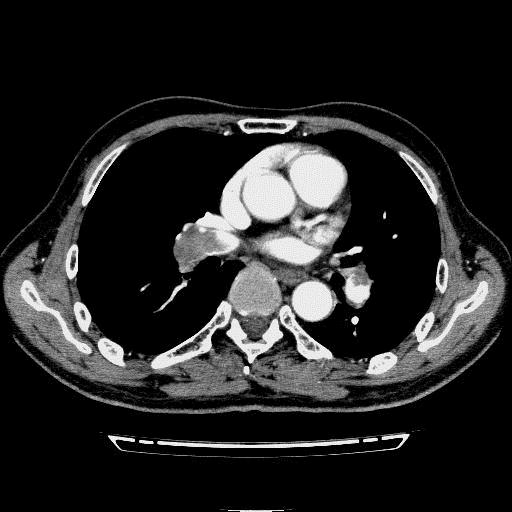

问题 病历摘要: 患者女性,83岁,活动后气促10天,伴心悸、咳嗽,咳少许白粘痰,感左侧胸痛,呈压榨样,与呼吸有关,但无放射痛,并发热,体温最高37.9℃,无明显规律性,无咯血、畏寒等。既往有系统性红斑狼疮病史,有吸烟史20年,已经戒烟20年。1月前始自觉双下肢易疲劳,但活动不受限。体查:T37.7℃,左肺可闻及啸鸣音和少许细湿啰音,心率123bpm,律齐,P2>A2,未闻及杂音。双下肢无水肿。 初步诊断考虑主要有哪些疾病? 提示:血气分析示: PO 65.7mmHg,PCO 45 mmHg HCO 22,胸片示:左下肺片状阴影,左下肺膨胀不全,左肋膈角变钝。

选项 A.支气管哮喘 B.COPD急性发作 C.左心功能不全 D.肺血栓栓塞症 E.肺癌 F.细菌性肺炎 G.肺结核 H.急性心肌梗塞

答案 BDFH